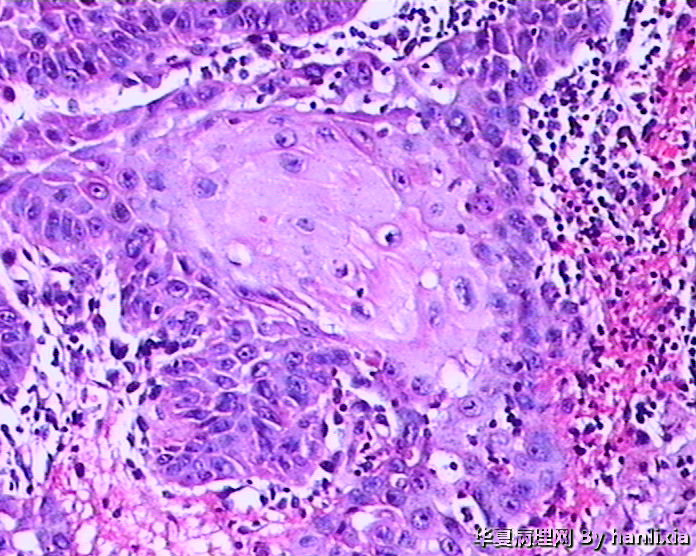

男性患者,50岁,发现面部皮肤(耳旁)肿物一年余,色黑。

高分化鳞状细胞癌

高分化鳞癌可能,也可能AK基础上发展而来的浅表型鳞癌?

部分区域突破基底膜,应该诊断鳞癌,由日光性角化发展过来的!